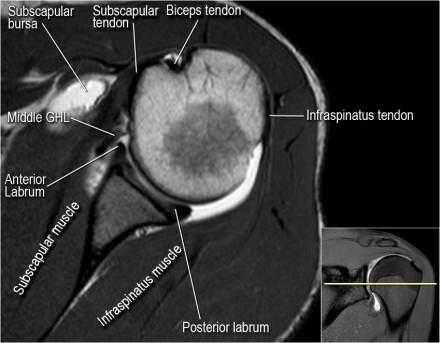

Нормальная анатомия плечевого сустава в аксиальных изображениях и контрольный список.

- уровень средней плече-лопаточной связки и передних отделов суставной губы. Поищите комплекс Буффорда. Изучите хрящи.

- вогнутость заднебокового края головки плечевой кости не следует путать с повреждением Хилл-Сакса, поскольку это нормальная форма для данного уровня. Повреждение Хилл-Сакса визуализируется только на уровне клювовидного отростка. В предних отделах мы сейчас на урвоне 3-6 часов. Здесь визуализируются повреждение Банкарта и его варианты.

- обратите внимание на волокна нижней плече-лопаточной связки. На данном уровне так же ищется повреждение Банкарта.